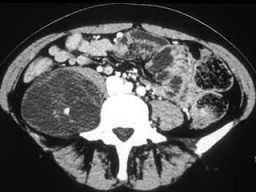

根据所提供的图像,最可能的诊断是()

• A.神经纤维瘤

• B.血肿

• C.脂肪肉瘤

• D.转移癌

• E.以上都不是